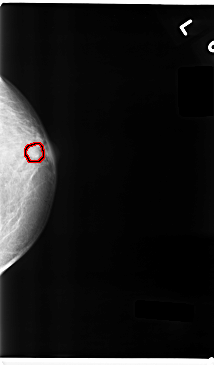

C_0237_1.LEFT_CC

LEFT_CC LINES 4736 PIXELS_PER_LINE 2776 BITS_PER_PIXEL 12 RESOLUTION 50 OVERLAY

FILE: C_0237_1.LEFT_CC.OVERLAY

TOTAL_ABNORMALITIES 1

ABNORMALITY 1

LESION_TYPE MASS SHAPE ROUND MARGINS CIRCUMSCRIBED

ASSESSMENT 4

SUBTLETY 4

PATHOLOGY BENIGN

TOTAL_OUTLINES 1

BOUNDARY